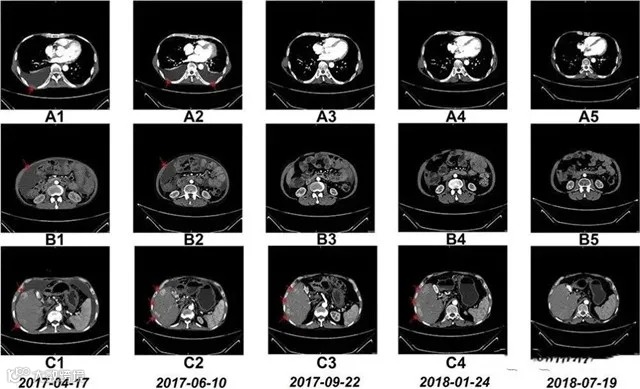

△NK细胞输入前和治疗期间的CT扫描结果

案例2:国内一名60岁的卵巢癌晚期患者,在接受了体外扩增,高度活化的同种异体NK细胞的临床治疗后,CA125水平从11,270降至580,所有腹水都消失了。此外,CT扫描的肿块体积减小,并且没有出现副作用。